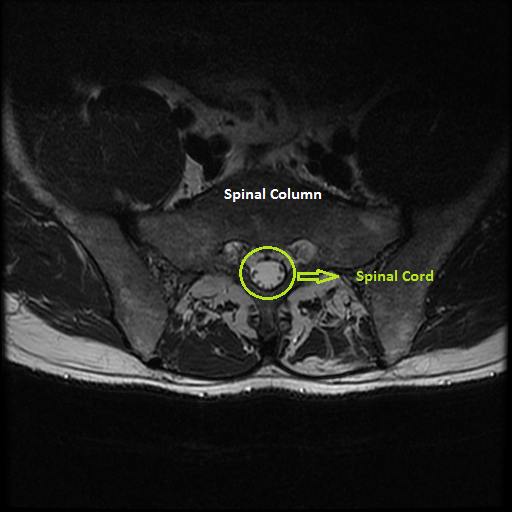

The first step is selecting the region of interest (ROI) from the MRI-defined lumbar muscles, which can be any among the erector spinae (ES) muscles, lumbar multifidus muscles (LMM) or psaos muscles, located either on the right or the left side of the spinal column [2, 5]. The user has to define the ROI by plotting a mask over the input image using livewire technique [21], as shown in Figure 2.

The livewire (or intelligent scissors) [21] is a semi-automatic image segmentation technique that allows the user to interactively select the ROI on an input image using mouse clicks along the contour of the ROI. When the user starts the selection of the ROI with a mouse click, a virtual wire is created linking the first clicked point (referred to as an anchor) to the point where the mouse is over, following a path that is as close as possible to image features detected as edges using Dijkstra’s lowest cost path algorithm. Figure 2 shows the result of a user segmentation using this tool.

The Livewire technique tends to work much slower in high resolution images, which would preclude its use. To resolve this, the input image was down sampled and the mask is defined in the low resolution image. The user defined mask is realized as a set of points in 2D coordinates, . Then using the set of points , the region inside the mask is cropped from the input image.